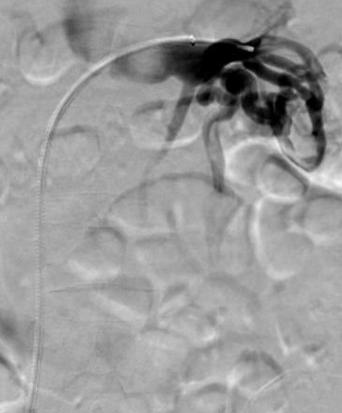

Reducing vessel selection time in a prostate artery embolization case

An 85-year-old man with a long-standing history of BPH presented with severe lower urinary tract symptoms (LUTS) and intermittent gross hematuria. Despite multiple medical treatments, including three transurethral resection of the prostate (TURP) procedures over the past two years, the patient’s condition had not improved. His International Prostate Symptom Score (IPSS) was 29 (severe), and his Urinary Quality of Life Score was 5 (unhappy).

SwiftNINJA steerable microcatheter use in moderate and high complexity angiography and/or embolization has routinely helped me to be successful and efficient. In 2019, I published my results, comparing steerable microcatheter to conventional microcatheter use in 40 procedures that involved moderate to highly difficult vessel selection.1 Statistically significant improvements in target vessel selection time—12 vs. 462.5 seconds (Figures 1a and b)—number of microwires used (0 vs. 2), total

Using a 2.4Fr SwiftNINJA through a 5Fr guide catheter, the left prostatic artery was selected in 12 seconds without a guidewire thanks to the steerability of the microcatheter tip. Proximal and then distal embolization of the left prostate artery with 300–500μ Embosphere microspheres (Merit Medical) was performed following the proximal embolization first, then embolize distal (PErFecTED) technique. The right prostate artery was then selected–again using the SwiftNINJA without a guidewire—in nine seconds and embolization was performed using the same technique.

Final angiography confirmed successful embolization of both left and right prostatic arteries. The patient was discharged the same day, with no hematuria or urinary retention reported since the procedure. At one month post-procedure, patient’s IPSS decreased from 29 to 7 and Urinary Quality of Life score decreased from 5 to 1.

Successful gonadal vein embolization through extremely tortuous anatomy

A 43-year-old female presented with chronic pelvic pain. Despite extensive diagnostic work-up, no definitive cause for the pain was found, except for

prominent left parauterine veins/varicosities and an enlarged left ovarian vein.

The patient was diagnosed with symptomatic pelvic venous reflux/pelvic congestion syndrome, and the plan was to proceed with venography and embolization. Due to extreme tortuosity of the gonadal venous vasculature preeminently, a 2.4Fr SwiftNINJA steerable microcatheter was used to efficiently navigate through the extremely tortuous vessels and into the inferior aspect of the left ovarian vein. Embolization was performed with sodium tetradecyl sulfate sandwiched in between packs of platinum microcoils.

Post-embolization digital subtraction venography demonstrated an appropriate angiographic result, with embolization of the left ovarian vein, but brisk antegrade blood flow in the left renal vein. The patient was discharged home in stable condition four hours post procedure, and experienced only mild flank discomfort for 24–36 hours post-procedure, relieved with ibuprofen. Her pelvic congestion syndrome symptoms markedly improved by the time she was seen for a post procedure office visit approximately six weeks later.

Figure 1. Left prostatic artery selected with SwiftNINJA steerable microcatheter. Initial internal iliac artery angiogram demonstrates Type 1 anatomy, with common origin of the left superior vesical artery and prostate artery (a). The microcatheter was moved from tip of 5Fr catheter to target vessel (distal aspect of main left prostate artery) in 12 seconds (b).